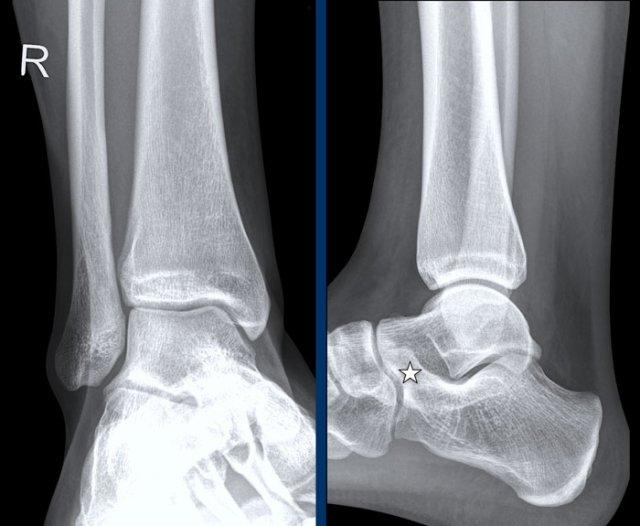

case 1 – distortion

The findings are:

- gãy xương thẳng đứng của mắt cá trong (mũi tên vàng).

Đây không phải là gãy xương do giật hay kéo, mà là gãy xương do đẩy. - Có thể có một avulsion của mắt cá ngoài (mũi tên trắng), nhưng điều đó chưa chắc chắn.

Tuy nhiên điều này không quan trọng vì chúng tôi sẽ trình bày ngay sau đây.

Gãy dọc mắt cá trong là gãy do lực đẩy.

Theo Lauge-Hansen, gãy xương xảy ra do lực khép trên bàn chân sấp.

Phía bên ngoài chịu lực căng cực độ với sự kéo giãn trên dây chằng bên ngoài.

Trong giai đoạn 1, có thể xảy ra đứt dây chằng bên ngoài hoặc gãy xương bong điểm bám (còn được gọi là Weber A).

Trong giai đoạn 2 luôn có gãy xương thẳng đứng của mắt cá trong và phải có hoặc là bong điểm bám của mắt cá ngoài hoặc đứt dây chằng bên vì các trình tự này luôn theo thứ tự này với giai đoạn 1 trước rồi đến giai đoạn 2.

Điều này có nghĩa là, dù chúng ta có thấy gãy xương ở phía bên ngoài hay không thì cũng không quan trọng.

Chắc chắn phải có tổn thương ở cả phía trong lẫn phía ngoài và chúng ta hiện biết rằng cổ chân không ổn định, vì vòng ổn định đã bị phá vỡ ở hai vị trí.

Here another unstable ankle fracture.

Theo Lauge-Hansen đây là giai đoạn SA 2.

Theo Weber đây là Weber A với gãy xương thêm ở mắt cá trong.